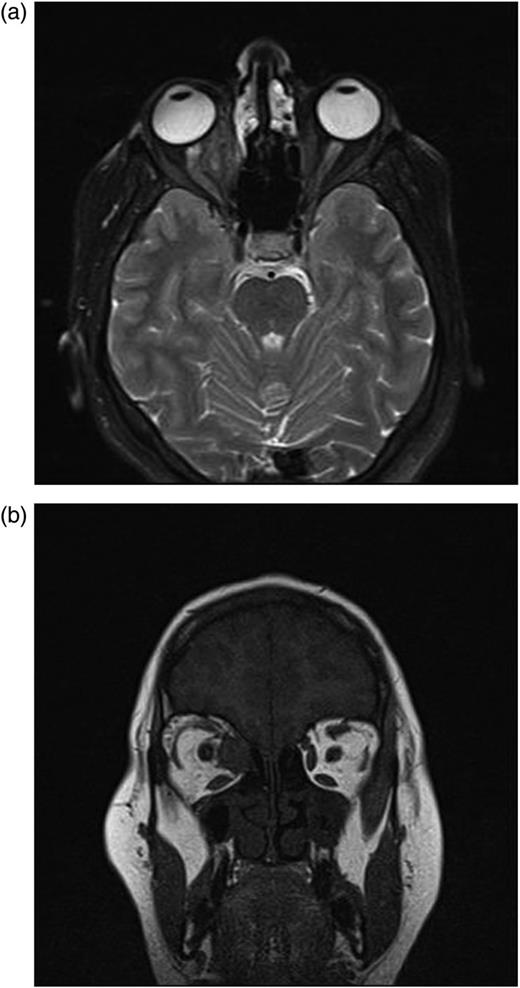

After second operation, in the first postoperative month, her ocular motilities were not restricted. Visual acuity was maintained at the same level (1/10). Control MR revealed no cystic structure except granulation tissue (Fig. 5a and b).

(a and b) After second operation, Control MRI in the first postoperative month shows granulation tissue.